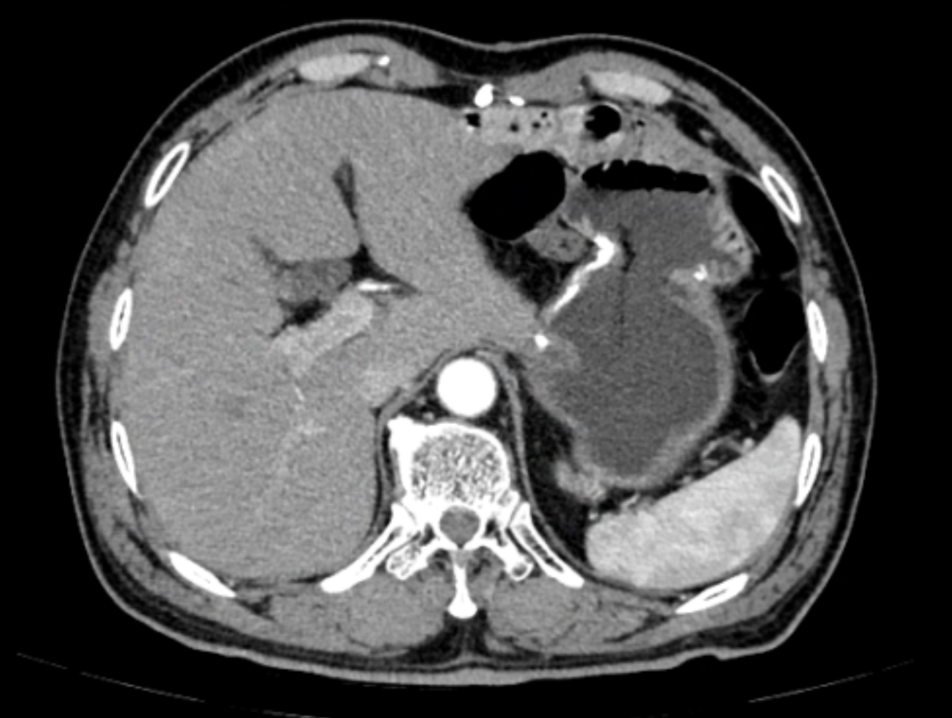

109.2.png

图2  术后复查CT

安全性:患者在整个围手术期治疗过程中耐受性良好,未报告与治疗相关的严重不良反应。

随访观察:完成所有治疗后,患者定期返院复查。截至目前,患者一般情况良好,未见明确的肿瘤复发或转移征象。